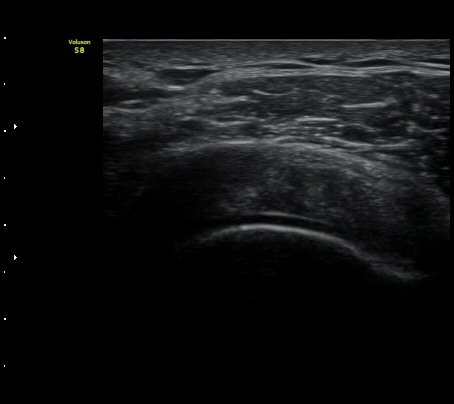

°ß°©ÇÏ±Ù°Ç »óºÎ Á¾´Ü¸é°Ë»ç»ó ¼Ò°áÀýÀÇÇÇÁú°ñÀÇ ºÒ±ÔÄ¢º¯È­¿Í °ß°©ÇÏ±Ù°Ç ¿¬°á¼º ¼Ò½ÇÀÌ

°üÂûµÊ(±×¸² 6, 7).